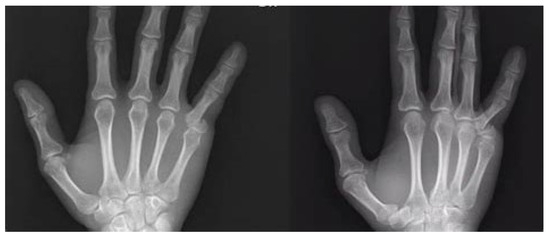

| “Extra Articular Fractures of The Proximal Phalanx of the Fingers: a Comparison of two Methods of Functional, Conservative Treatment” Franz T. et al., 2012 [25] | Prospective Randomized Multicenter Study with 66 subjects (49 years avg. age), including 16 males and 16 females, with P1 extra-articular fractures. Fractures treated conservatively with MCPJ block at 70–90° flexion, LUCA splint, and forearm cast. IPJ were free to move. Immobilization lasted 4 weeks (forearm cast) and 4.5 weeks (LUCA splint). | No significant differences in TAM, AROM, patient satisfaction, or correct fracture healing. 2 cases of CRPS complications in the Forearm cast group; no complications in the LUCA group. | Both splints were effective in treating P1 fractures with minimal differences in patient outcomes. LUCA splint provided better wrist ROM without complications. |

| “Non-Surgical Management of Isolated Proximal Phalangeal Fractures With Immediate Mobilization” Byrne B. et al., 2020 [27] | Prospective Observational Study. 122 subjects (median age 35 years; males avg age 30, females avg age 48) with P1 extra-articular fractures. Fractures were treated conservatively with a dorsal orthosis, MCPJ block at 70–90° flexion, and IPJ free to move. Treatment duration varied from 6 weeks until reaching adequate outcomes. | Majority of participants had a good/excellent outcome. Patients were discharged with a median of −4° PIPJ extension, 94° flexion, and 253° TAM. Median pain score was “0”. | Conservative treatment with immediate mobilization provided excellent outcomes, especially for younger patients, with minimal pain and high functional recovery. |

| “Conservative Treatment of Fractures of The Proximal Phalanx, an Option Even for Unstable Fractures” Held M. et al., 2013 [29] | Case Series Study. 23 subjects (median age 36 years; 18 males, 5 females) with P1 extra-articular fractures. Fractures treated conservatively with a dorsal slab, MCPJ block at 70–90° flexion, and syndactyly with the adjacent finger. Treatment lasted 3 weeks. | Approximately 91% of fractures maintained acceptable reduction within the slab, with a median fracture angulation of 4°. Complications: 5 extensor lags, 4 cases of bone reduction, and 20° PIPJ stiffness in 2 patients. | Conservative treatment was highly effective, even for unstable fractures, maintaining reduction and achieving positive outcomes in the majority of cases. |

| “Traction Splints: Effective Nonsurgical Way of Managing Proximal Phalanx Fractures” Ashok R. K., 2009 [30] | Case Series Study. 30 subjects (aged 20–50 years; 29 males, 1 female) with P1 extra-articular and intra-articular fractures (P1 surface only). Fractures treated conservatively with dorsal orthosis and dynamic traction given by a 90° outrigger. MCPJ block held at 70–90° flexion. Treatment lasted 4 weeks. | Patients reported very good outcomes, with minimal pain and deformities. Patients ≤ 50 years had significantly better outcomes. | Dynamic traction splint provided very good outcomes, particularly in younger patients, with minimal pain and deformities. |

| “Dynamic Treatment for Proximal Phalangeal Fracture of The Hand” Rajesh G. et al., 2007 [31] | Case Series Study. 32 subjects (≤50 years avg. age; 20 males, 12 females) with P1 extra-articular fractures. Fractures treated conservatively with thermoplastic MCP block splint, wrist held at 20–30° extension, MCPJ block held at 90° flexion. Treatment lasted 3–4 weeks. | According to Reyes and Latta and Belsky classifications, outcomes were excellent for all subjects. | Dynamic splinting was highly effective, with all patients achieving excellent outcomes, confirming its utility for P1 fractures. |